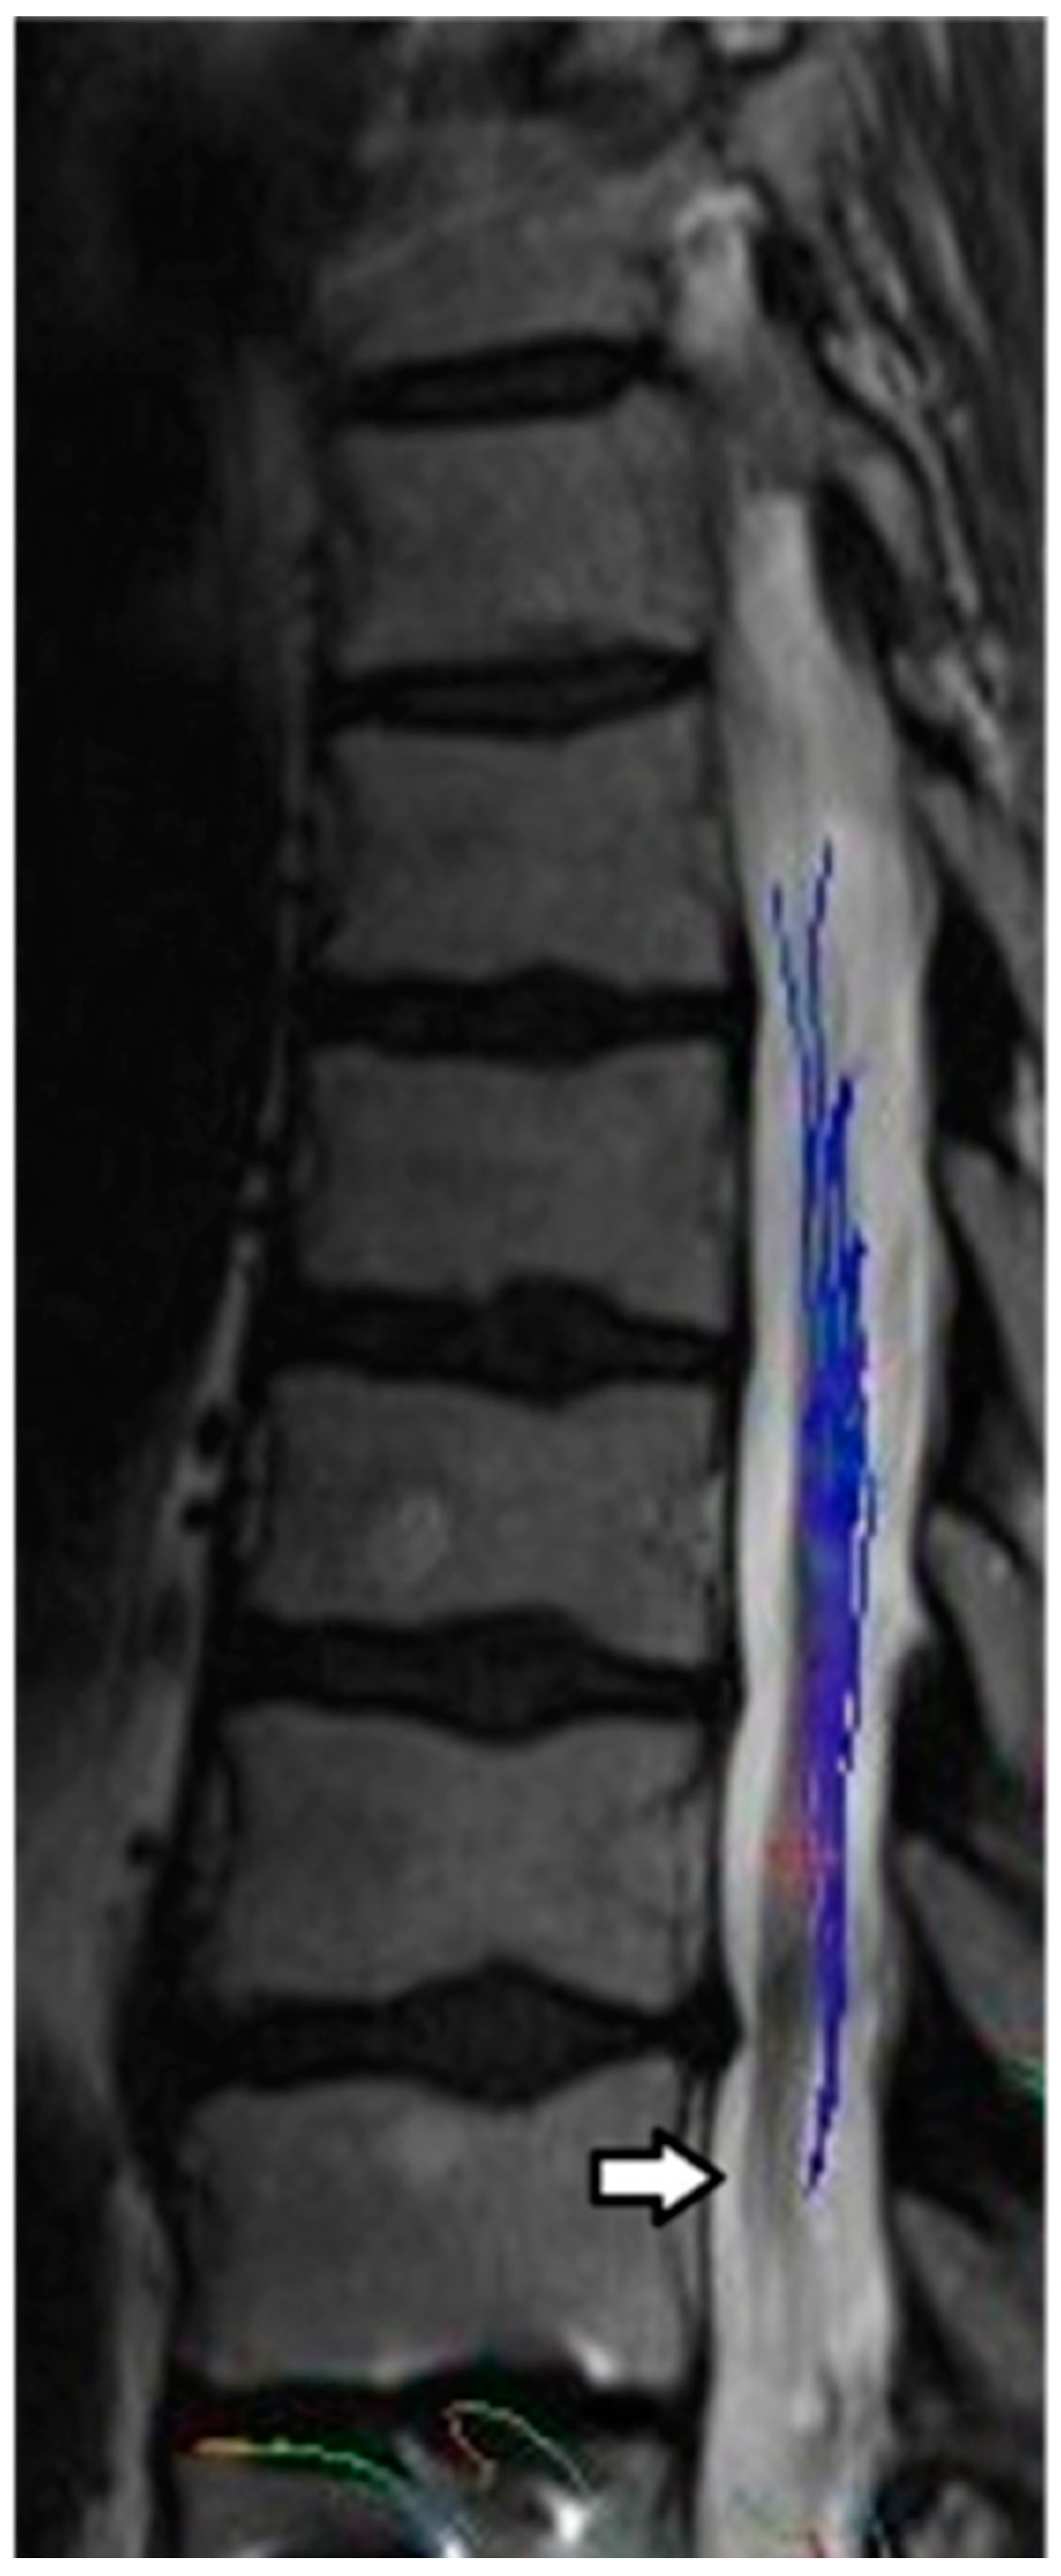

3.2. Promise and Challenges of MRI Tractography